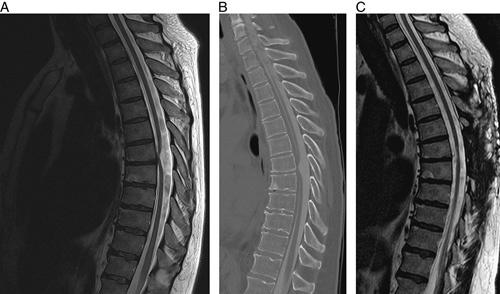

Idiopathic Spinal Cord Herniation Associated With a Thoracic Disc Herniation: Case Report, Surgical Video, and Literature Review.

ISCH is an infrequent condition that can cause progressive myelopathy leading to severe neurological dysfunction. This condition is characterized by ventral displacement of the spinal cord across a defect in the dura, either congenital or acquired, resulting in vascular compromise and adhesion that subsequently causes injury to the spinal cord. We present the management of such a patient, in addition to a review of the literature regarding management of ISCH.

This patient underwent surgery using the dural graft sling technique for repair of the dural defect and restoration of normal spinal cord position within the thecal sac. A review of the literature revealed a total of 171 patients supplemented by our 1 patient, which were then analyzed.